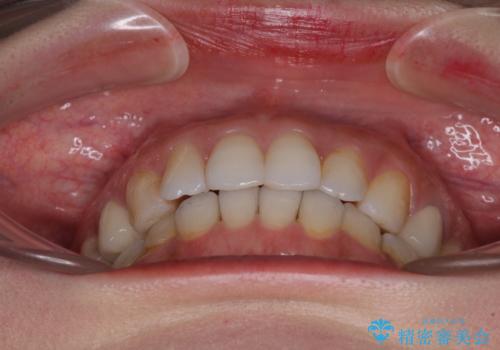

- 失活により変色した歯と不揃いな口元を気にして来院された患者様です。

口元をインビザラインにより歯列を整え、その後に失活している奥歯をオールセラミッククラウンにて補綴治療することとしました。

長時間のマウスピース装着と、患者様自身でのゴムかけに協力いただき、自然な口元に仕上げることができました。

気になっていた変色した歯もオールセラミッククラウンで本物の歯のようになり、患者様には大変満足していただきました。